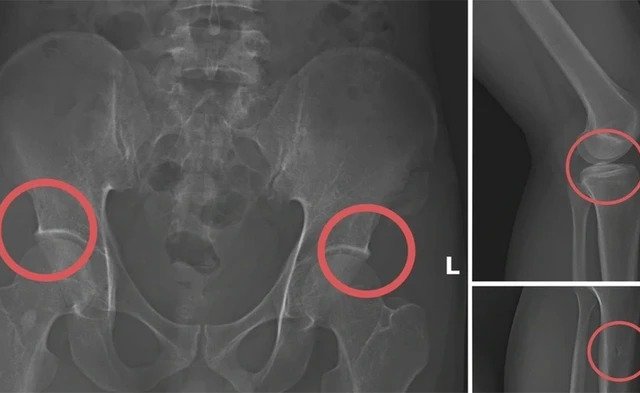

Ngâm chân trong đá để đòi tiền bảo hiểm, thanh niên vừa cụt chân vừa phải đi tù

Để lừa tiền 5 công ty bảo hiểm, Trương ngâm chân trong đá lạnh 10 tiếng; hậu quả là anh ta bị cắt cụt chân...